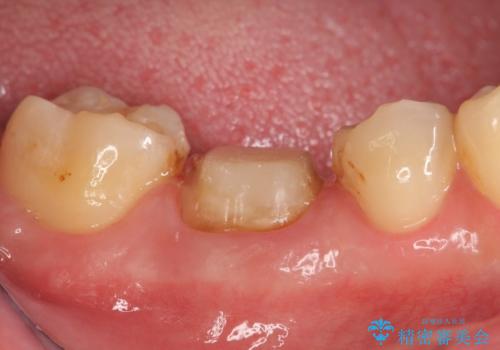

- 右下の奥歯の鈍い痛みがずっと続いているので診て欲しいといらっしゃった方の症例です。

検査の結果右下6に根尖病変を認めたため、再根管治療を行いました。

その後症状の消失を確認し、オールセラミッククラウンによる補綴を行いました。

- オールセラミッククラウン…¥100,000、仮歯…¥10,000、ファイバーコア…¥20,000費用は治療当時の料金となります